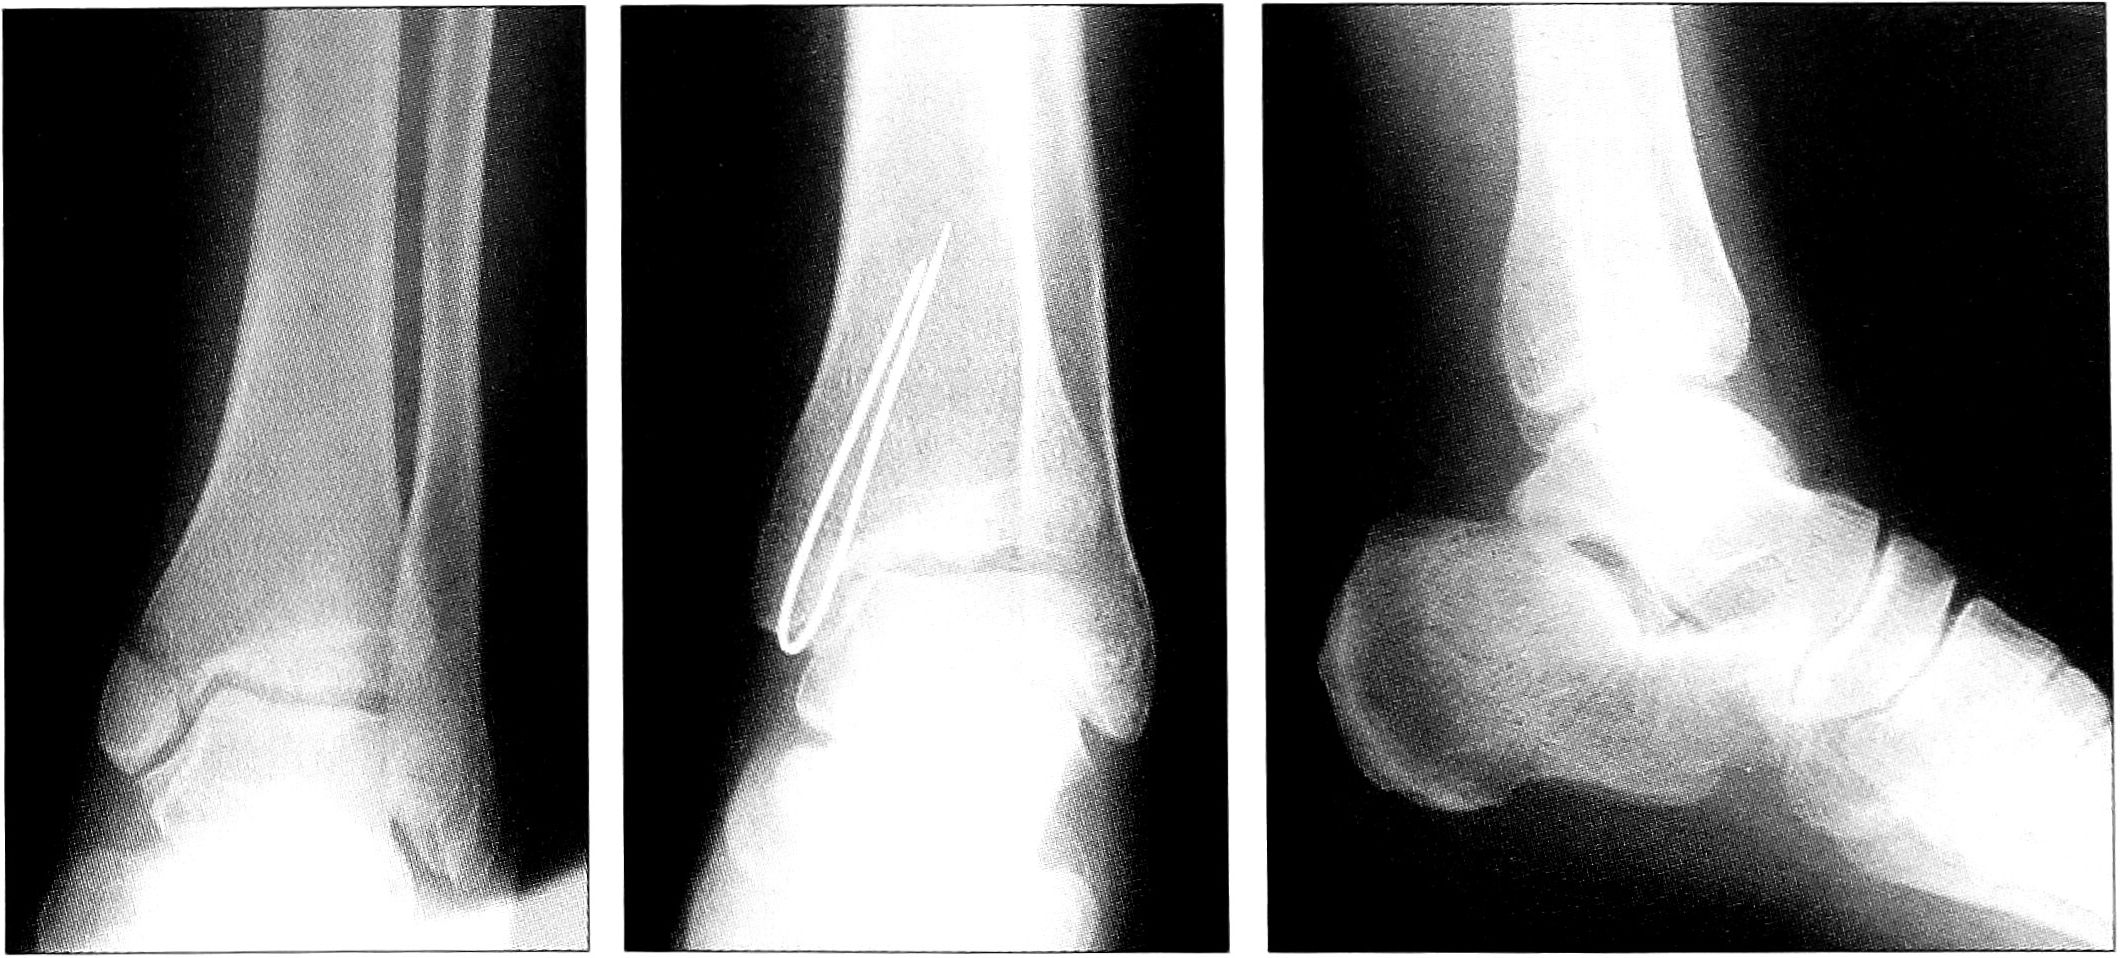

У 10 больных с переломами внутренней лодыжки после закрытой репозиции был произведен перкутанный остеосинтез V-образной спицей. Примером может служить больная Е.,20 лет, которой через 2 дня после травмы (апикальный перелом внутренней лодыжки) под контролем ЭОП выполнен перкутанный остеосинтез V-образной спицей; на 2-е сутки после операции начаты активные занятия лечебной гимнастикой без внешней иммобилизации (рис. 3).

Рис. 3. Перкутанный остеосинтез V-образной спицей при переломе внутренней лодыжки.